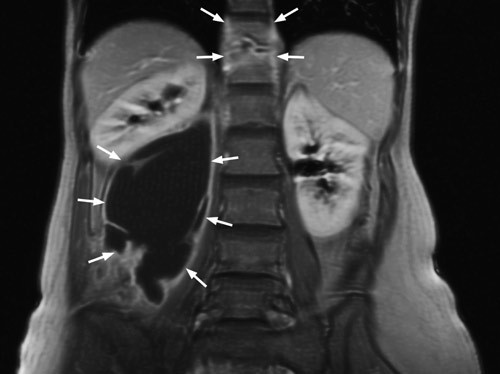

Hun hadde en senkningsreaksjon på 49 mm/t. Andre orienterende blodprøver, inkludert hivtest, var normale. Røntgen thorax og urindyrking for mykobakterier var negative. MR abdomen viste funn som ved spondylodiskitt i nivå Th11/Th12 med en stor senkningsabscess i høyre m. psoas (til venstre). Abscessen målte ca. 14 cm kraniokaudalt og strakte seg kaudalt i høyde med virvelcorpus L5. Til høyre ses et tverrsnitt av abscessen. Mikroskopi av abscessmaterialet viste ingen funn av syrefaste staver. Dyrking og polymerasekjedereaksjon (PCR) viste funn av Mycobacterium tuberkulosis. Det ble drenert ca. 350 ml puss og startet med langvarig tuberkulostatikabehandling. Kvinnen følges regelmessig med polikliniske kontroller.